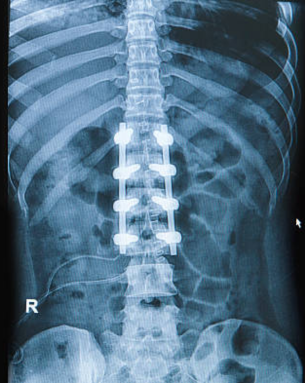

Spinal trauma management involves surgical and non-surgical interventions to stabilize the spine and protect neural elements. Techniques include instrumentation with rods, screws, and plates, spinal fusion, and in some cases, vertebroplasty or kyphoplasty for vertebral compression fractures. The approach depends on injury severity, location, and neurological involvement, aiming to restore spinal alignment and function.